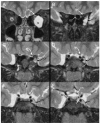

Results: A 6-year-old patient was admitted for right otomastoiditis and thrombosis of the sigmoid and transverse sinuses, as well as the proximal portion of the internal jugular vein. Radiological examinations revealed a left orbital mass (22 × 14 mm) compatible with asymptomatic orbital meningocele (MC) herniated from the superior orbital fissure (SOF). The child underwent a right mastoidectomy. After the development of symptoms and signs of intracranial hypertension (ICH), endovascular thrombectomy and transverse sinus stenting were performed, with improvement of the clinical conditions and reduction of the orbital MC. The systematic literature review encompassed 29 publications on 43 patients with spontaneous orbital MC. In the majority of cases, surgery was the preferred treatment.